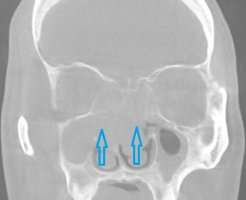

코 물혹 수술 비용 오래된 두통, 코가 막혀서, 콧물이 지속적으로 나와서 병원에 찾아 왔는데 내시경 검사에서 "코에 물혹이 있다"라는 이야기를 들으셨나요? 코에 생긴 혹을 조직검사로 확인해보면

코 물혹 수술비용 축농증 수술후 부비동 물혹 염증수술 코 물혹 재발 코에 물혹 부비동염 수술